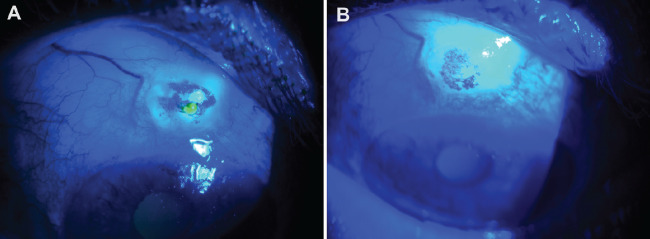

小梁切除术是用于降低青光眼患者眼压(IOP)的主要手术方法。尽管效果显著,但也可能导致严重的并发症,包括眼压过低、脉络膜渗出、睑板腺炎和睑板腺渗漏。眼泡渗漏需要及时的药物或手术干预,以防止出现严重的并发症,如眼泡炎和眼泡相关性眼内炎。近年来,胶原交联术(CCL)的适应症已从角膜异位疾病扩展到角膜炎和眼泡渗漏等各种眼部疾病。在此,我们介绍一例 70 岁男性患者的病例,他患有血管囊性眼泡渗漏。患者在接受结膜 CCL、局部庆大霉素、多佐胺/噻吗洛尔复方制剂和治疗性隐形眼镜的综合治疗后,眼泡渗漏停止,眼压上升。

Trabeculectomy is a primary surgical procedure used to reduce intraocular pressure (IOP) in patients with glaucoma. Despite its effectiveness, it can lead to significant complications, including hypotony, choroidal effusion, blebitis, and bleb leaks. Bleb leaks require prompt medical or surgical intervention to prevent severe complications such as blebitis and bleb-associated endophthalmitis. In recent years, the indications for collagen cross-linking (CCL) have expanded beyond corneal ectatic diseases to include various ocular conditions such as keratitis and leaking blebs. Here, we present the case of a 70-year-old male patient with a leaking avascular cystic bleb. Following treatment with a combination of conjunctival CCL, topical gentamicin, a dorzolamide/timolol combination, and a therapeutic contact lens, the patient experienced cessation of bleb leakage and an increase in IOP.